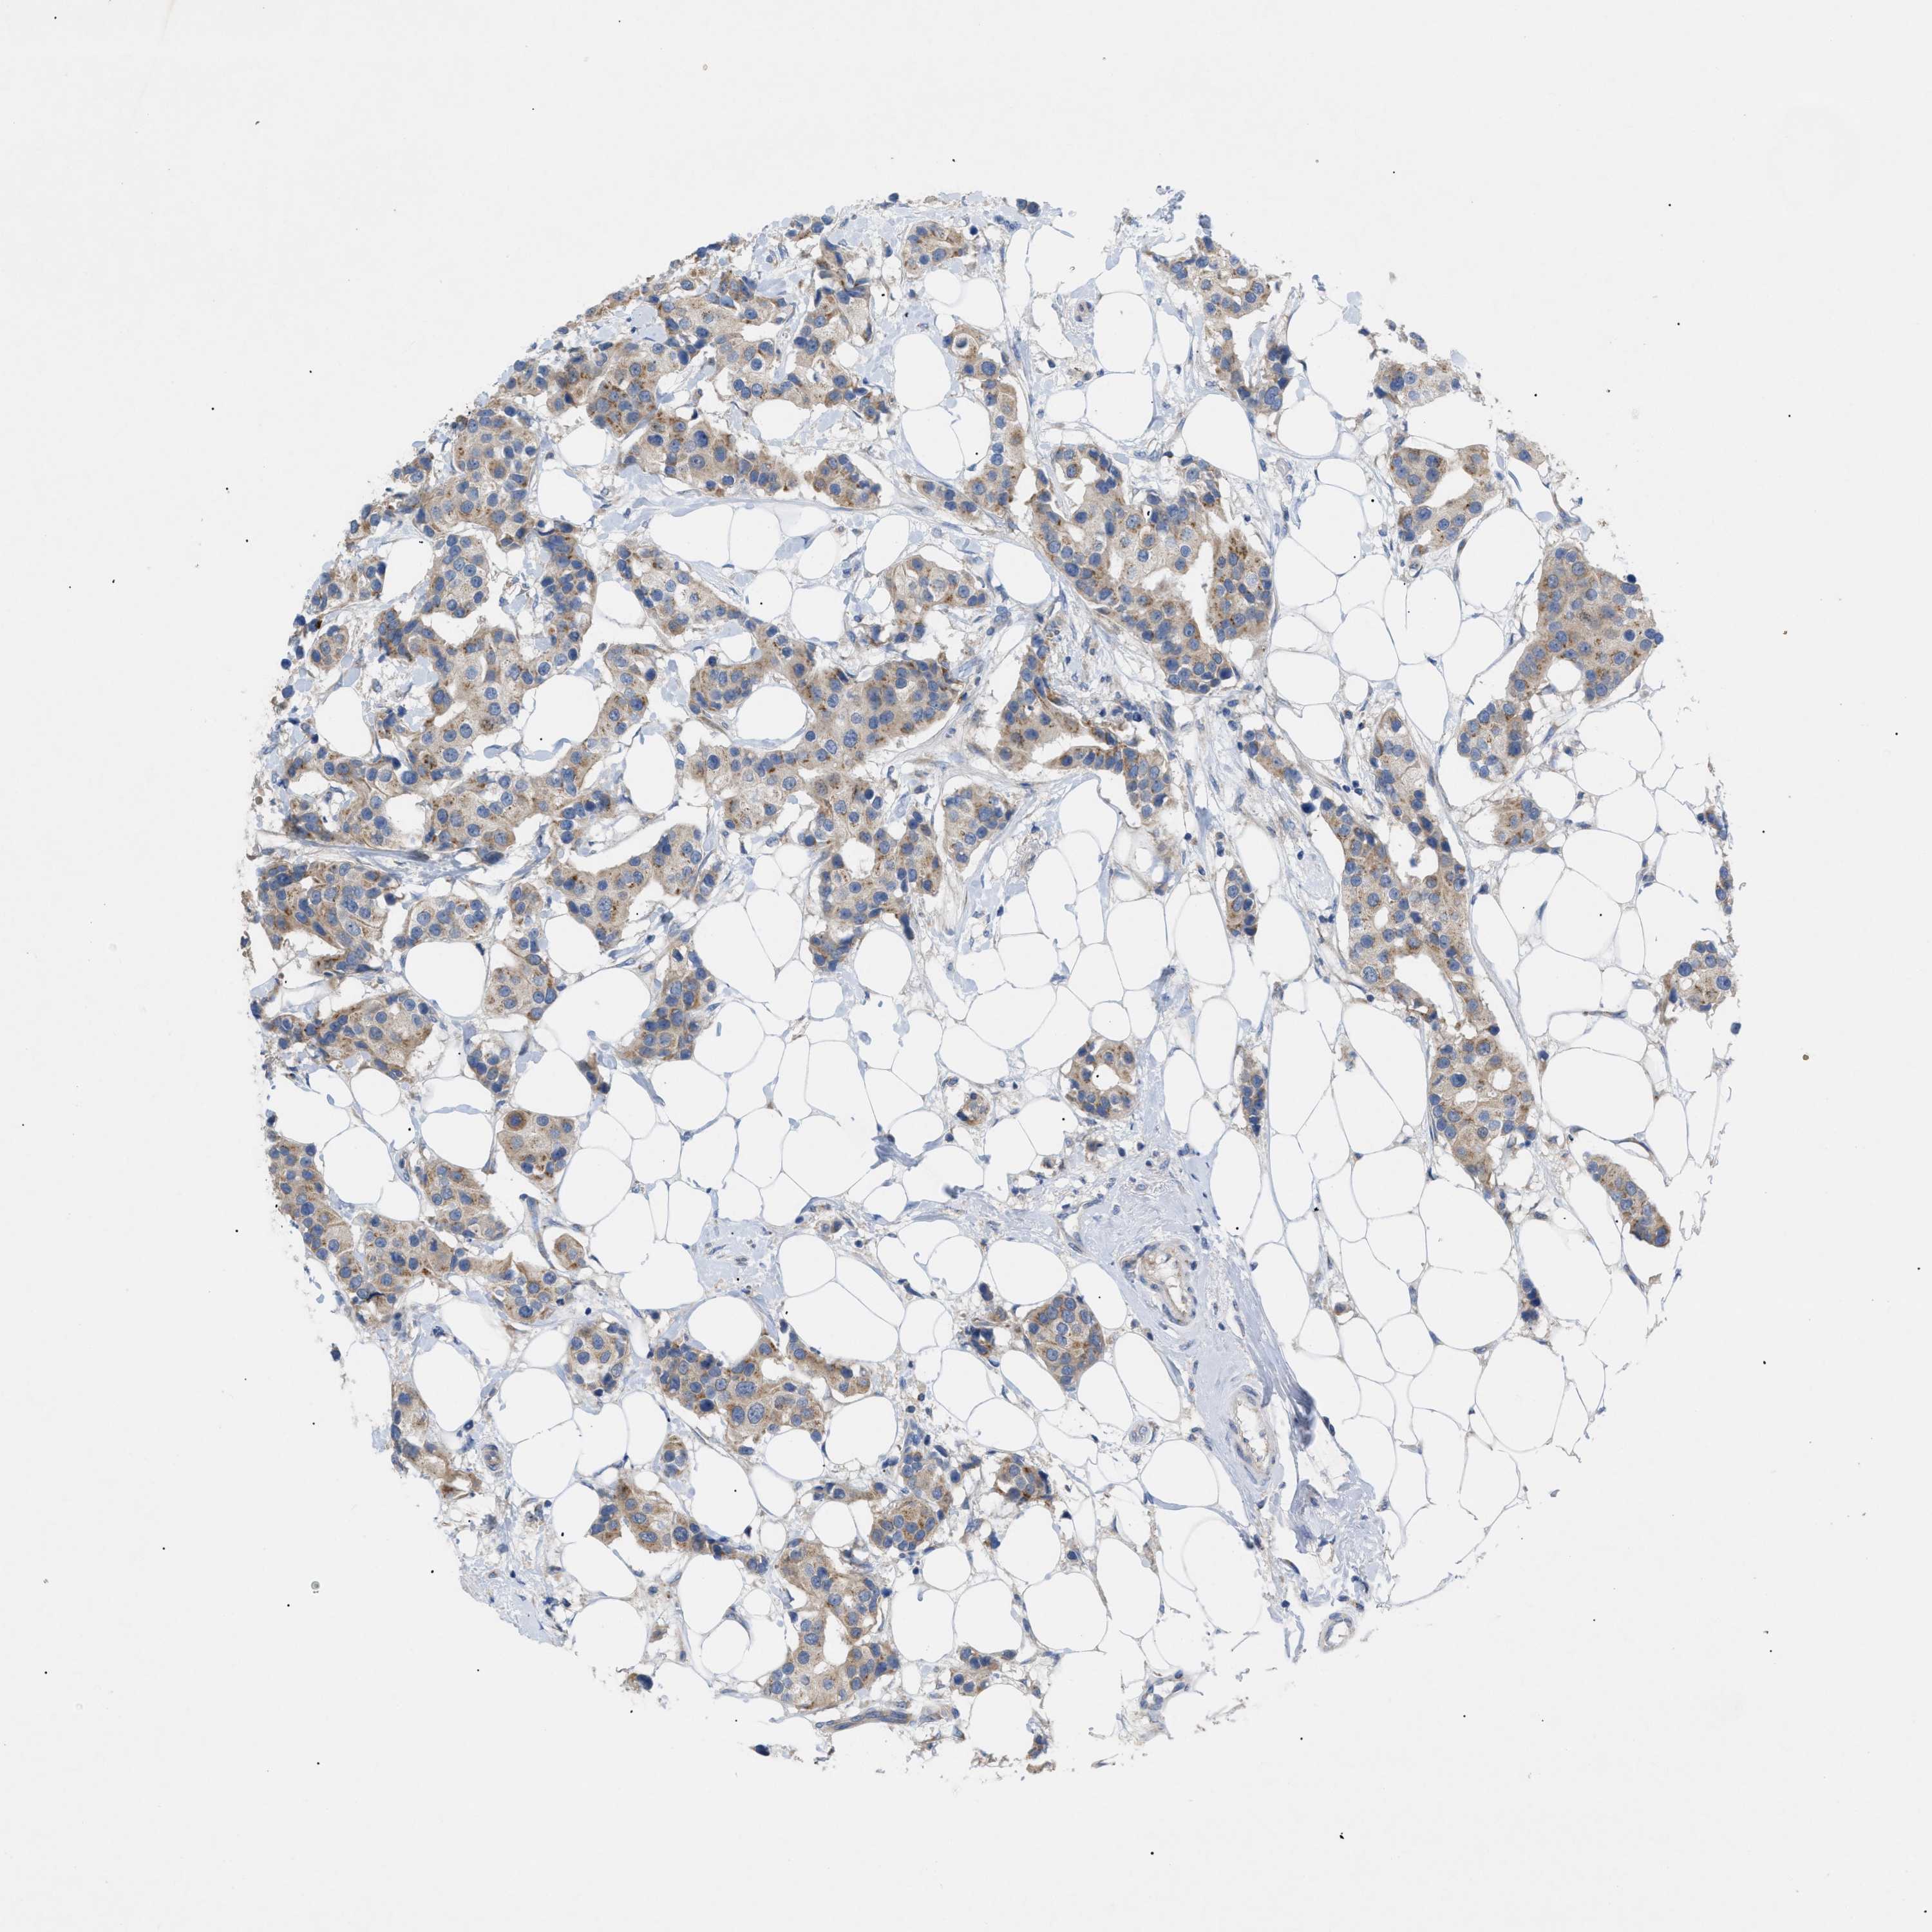

CANCER BREAST CANCER Show tissue menu

BRCA TCGA BRCA VALIDATION PROTEIN EXPRESSION